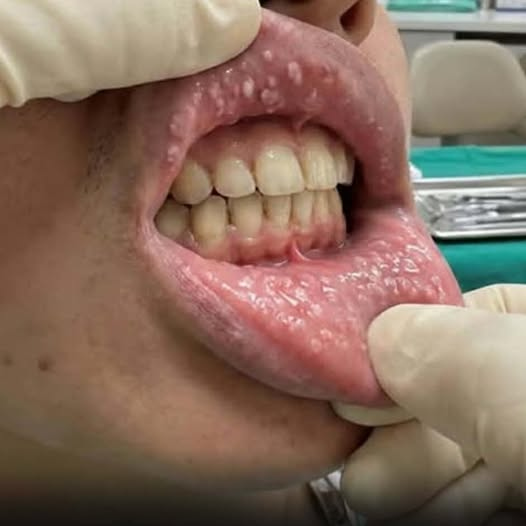

1. Fordyce Glands

One of the most common benign causes of bumps on the lips is Fordyce glands. These are tiny sebaceous (oil) glands that naturally occur on the lips and other mucosal areas. Unlike typical sebaceous glands associated with hair follicles, Fordyce glands appear on hairless regions of the lips and are entirely normal.

- Appearance: Small, white or yellowish spots

- Symptoms: Usually painless and non-inflamed

- Treatment: None required; harmless

Fordyce glands are not contagious and do not pose any health risk. They can be more visible in adults with lighter skin, and while they may cause cosmetic concerns for some, they generally remain stable throughout life.